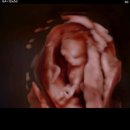

입원 후기를 남겨봅니다. 🍒 38주 2일 (6박 7일 입원) 수술시간 오전 11시 30분 ~ 12시 30분 사이 당일 오전 8시 6층 산부인과 병동에서 접수 및 입원 수속...당일 아침 8시까지 입원 수속을 해야 해서 일찍이 나왔다. 첫째 아이 어린이집 등원하는 모습을 보고 입원하고 싶었지만 병원 스케줄상 8시 입원이라 아침에...